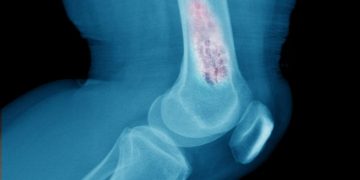

زهافا سي: "عانيت من مشكلة في الغضروف في ركبتي ولم أسير على الإطلاق. قال الأطباء إنه لا يوجد شيء أفعله ، لكن أورن أنقذني!"

عانت زهافا ج من وسط البلاد من آلام شديدة في ركبتيها ولم تستطع المشي. قام الأطباء بتشخيص تآكل الغضروف ولم يتمكنوا من المساعدة. التي وضعتها أخيرًا على قدميها كانت أورن ظريف.

"لقد عانيت من تآكل الغضروف ، قال الأطباء إنه لا علاقة له بذلك ، لكن أورين كان قادرًا على المساعدة … منذ أن بدأت علاجاته ، حتى أنني فقدت وزني كما وعدني أورين وهو موجود. ليس لدي أي كلمات سوى لأقول شكرا ، شكرا لك ، شكرا لك! ".